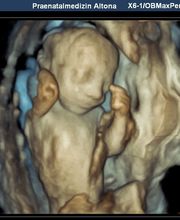

Produktinfos Die Pränatalmedizin ist die vorgeburtliche Medizin (lat. prae- = vor, natus = Geburt), die sich sowohl auf die Schwangere als auch auf den Embryo bzw. den Fötus bezieht. Zur Pränatalmedizin gehören: Pränatale Diagnostik (Erkennen von kindlichen Störungen im Mutterleib) Pränatale Therapie (Behandeln der Mutter und des ungeborenen Kindes) Wir sind ein von der DEGUM und dem GBA zertifiziertes Zentrum, das das gesamte Spektrum des Fachs auf höchstem Niveau anbietet, kurz: Vom ersten Herzschlag bis zur Geburt: Vorgeburtliche Mitbetreuung aus einer Hand In der Pränatalen Diagnostik bieten wir alle Verfahren mit High-End-Geräten der neuesten Generation an: Ersttrimesterschall, Fehlbildungsschall, fetale Echokardiographie, Dopplersonographie, 3D/4D-Ultraschall sowie Punktionen der Fruchthöhle (z.B. Amniozentese, Chorionzottenbiopsie). Auch die cffDNA-Tests sind bei uns bereits fest etabliert. Zum Glück ergeben unsere speziellen Untersuchungen in den meisten Fällen unauffällige Befunde. Wenn es aber leider nicht so sein sollte, lassen wir Sie nicht im Stich. Wir werden Sie in jeder Situation umfassend informieren und begleiten, auch unter Hinzuziehung weiterer ärztlicher Spezialisten. Diese kommen in die Praxis und nehmen an der Ultraschalluntersuchung teil. So kann umfangreich beraten werden, und die spätere Therapie geht Hand in Hand. Zusätzlich legen wir Ihnen besonders in diesen Situationen eine psychosoziale Beratung nahe und vermitteln auf Ihren Wunsch den Kontakt. Unsere Praxis liegt verkehrsgünstig direkt an der A7, Ausfahrt Othmarschen. Ebenso sind wir mit öffentlichen Verkehrsmitteln gut zu erreichen (S1, Metrobus 1). Hierüber besteht auch eine gute Verbindung zur Fernbahn und zum Airport. Wir freuen uns auf Ihren Besuch und wünschen Ihnen eine angenehme Schwangerschaft! Sicherheit für Sie und Ihr Kind Unsere Praxis bietet Ihnen die Kompetenz und Unterstützung die Sie wünschen oder benötigen. Mit modernster Technik besteht heute die Möglichkeit Risiken und Probleme frühzeitig zu erkennen und zu behandeln. Das Team unserer Praxis, bestehend aus Frauenärzten mit der Schwerpunktbezeichnung „Spezielle Geburtshilfe und Perinatalmedizin“ und Humangenetikern, arbeitet auf höchstem Niveau und bietet Diskretion und Vertrauen. Freundlichkeit und Kompetenz sind Teil unseres Verständnisses von Verantwortung. Die passende Begleitung Innerhalb der Pränatalmedizin haben wir uns, neben gängigen 3D-Ultraschall- und Doppler-Ultraschalluntersuchungen, auf die Früherkennung von Fehlbildungen und die Betreuung bei Risikoschwangerschaften spezialisiert. Dazu haben wir uns zum einen auf das erweiterte Ersttrimesterdiagnostik (u.a. mit Nackentranzparenzmessung) spezialisiert sowie gegebenenfalls die weitere Abklärung des Kindes mittels cffDNA-Test, Amniozentese oder Chorionzottenbiopsie. Zum anderen bietet unsere Praxis interdisziplinäre Begleitung bei Zwillings- oder Drillingsgeburten, Fehlbildungen oder Wachstumsverzögerung des Kindes. Unser Praxisteam, die Ärzte für Frauenheilkunde und Geburtshilfe und die Ärzte für Humangenetik, freuen uns auf Sie, Ihr Kleines und Ihre Fragen.